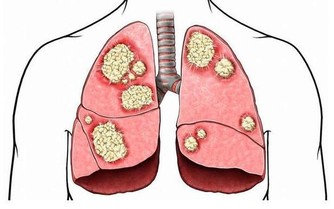

據衛生署統計資料,大腸癌(包括直腸癌及結腸癌)占國人癌症死因的第3名,而且10年前的平均罹患年齡為62歲,最近降低為54歲,在美國南加州大學擔任副教授的陳昌平醫師更預測:「10年後,年齡層會降到45歲左右,因此民眾不能不注意。」

陳 昌平說明大腸癌的成因:「簡單說,是先有便祕,接著產生息肉,再病變成大腸癌。」大腸是由升結腸、橫結腸、降結腸及乙狀結腸等所構成,左側的大腸管徑比右 側大腸窄,當有腫瘤發生時,就會出現腸阻塞而引起便祕、腹脹甚至腹痛的情形。因為糞便大多在左側的結腸成形,因此如果阻塞的狀況嚴重的話,所排出的糞便就 會有時還會參雜血絲, 嚴重到便祕及解血便情形。

陳昌平認為,大腸癌的成因與飲食最有關係,其次是遺傳,因此經常大魚大肉或有家族病史者,一定要 每年接受檢查,及早發現及早治療。許多研究皆顯示,攝取過多的動物性脂肪會增加罹患大腸癌的機會,因此應多吃高纖食物,食物纖維有助於吸收腸內水分,使糞 便體積增大,刺激腸子蠕動,方便排泄,避免便祕且縮短致癌物質留在腸內的時間,降低罹癌機率。